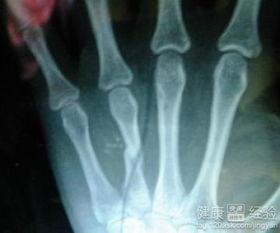

骨折了,是不是心情down到了谷底?别担心,今天就来给你支个招,让你在恢复期间也能吃得开心,那就是——哈密瓜!是的,你没听错,这个甜蜜的水果竟然能助你一臂之力,加速恢复。下面就让我带你从多个角度来了解为什么骨折恢复期间吃哈密瓜是个不错的选择。